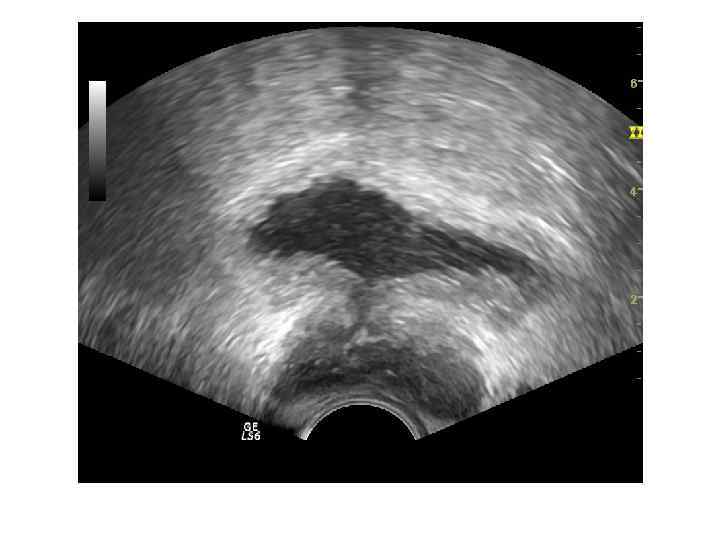

Абсцесс предстательной железы имеет достаточно характерную ультразвуковую картину: одно или несколько объемных образований в паренхиме простаты чаще округлой или овоидной формы с толстой слоистой стенкой и неоднородным жидкостным содержимым, с усилением сосудистого рисунка по периферии. ТРУЗИ болезненно!!